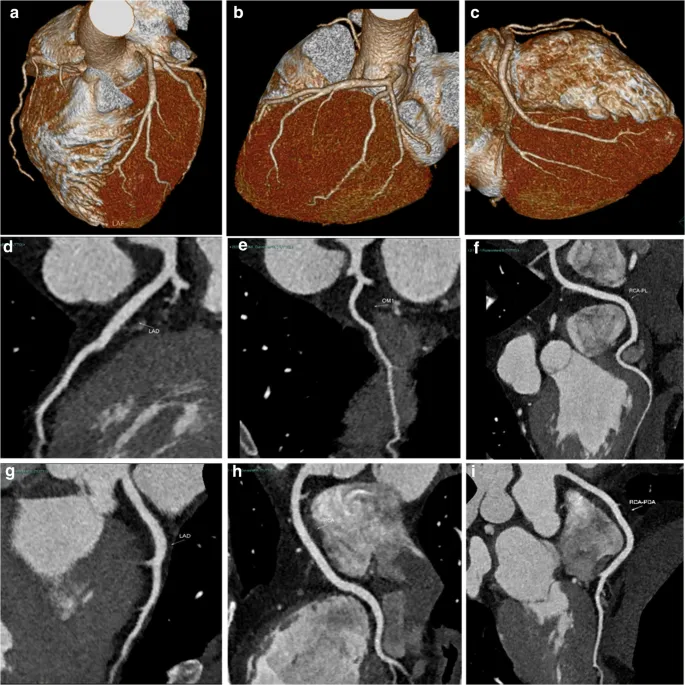

2. Triple Rule-Out CT in Acute Chest Pain By Dr. Resham Singh Thakur

Confused about when to use Triple Rule-Out CT in patients with acute chest pain?

This Conceptual Radiology session breaks down the role of CT in differentiating between acute coronary syndrome, pulmonary embolism, and aortic dissection — especially in low to intermediate-risk patients.

📌 Key takeaways:

➡️ Stepwise evaluation of acute chest pain

➡️ Role of ECG, biomarkers, and imaging

➡️ When to consider Triple Rule-Out CT

➡️ Exam-smart flowchart you must know